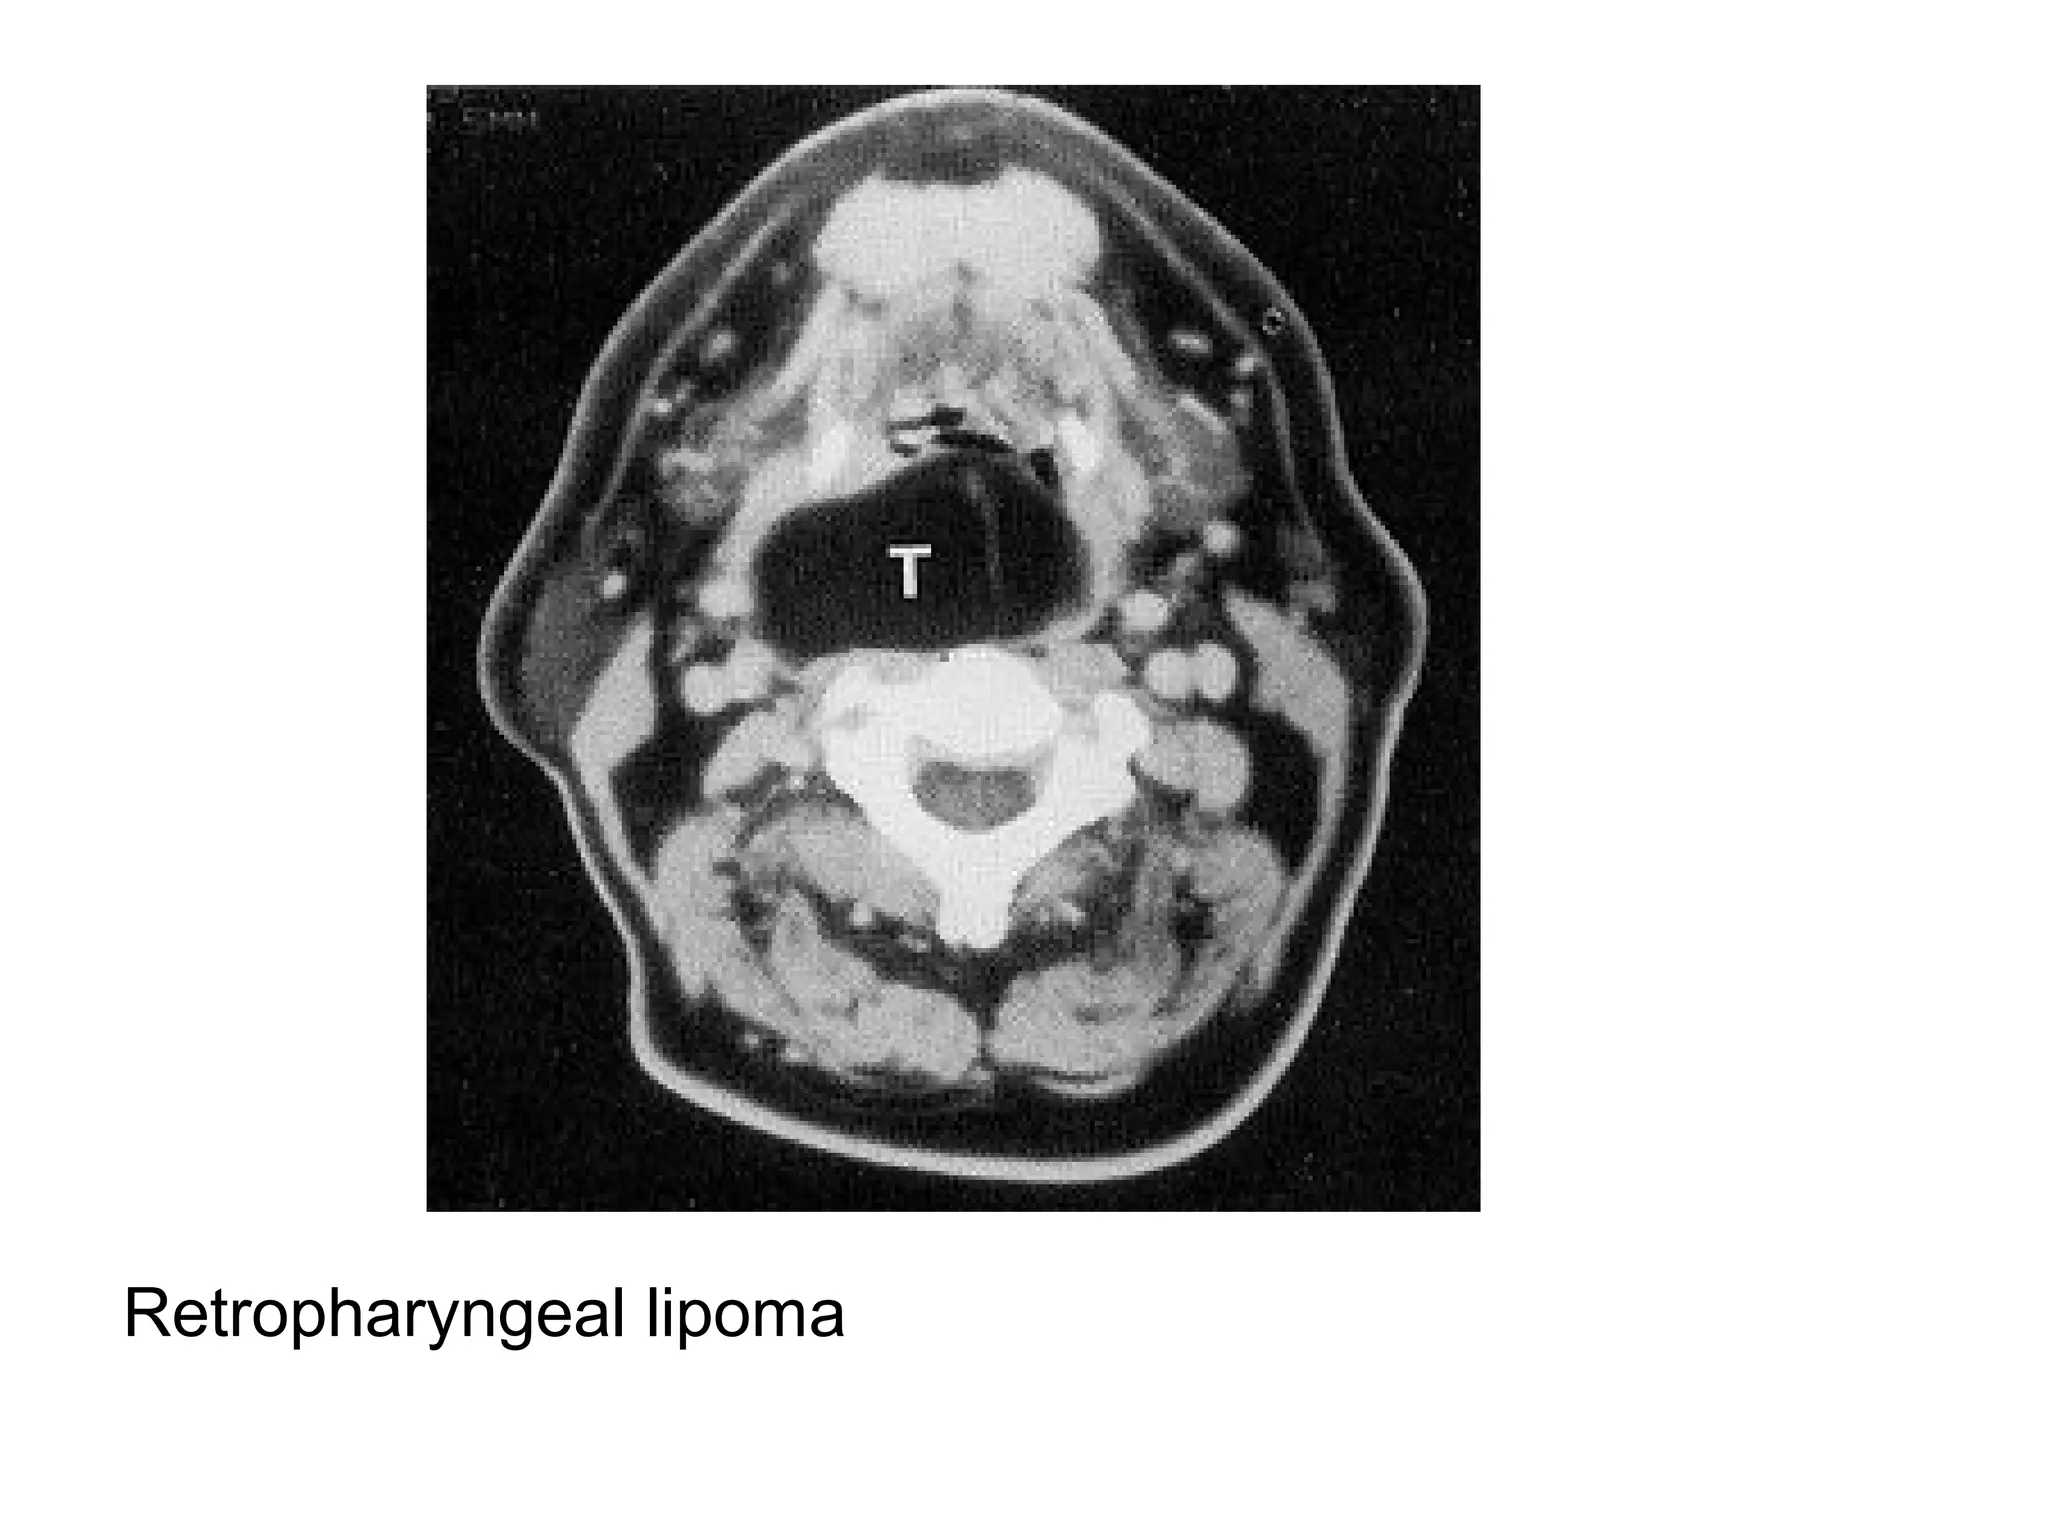

Retropharyngeal lipoma